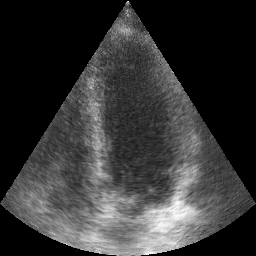

Transthoracic echo is one of the most common means of cardiac studies in the clinical routines. During the echo exam, the sonographer captures a set of standard cross sections (echo views) of the heart. Each 2D echo view cuts through the 3D cardiac geometry via a unique plane. Consequently, different views share some limited information. In this work, we investigate the feasibility of generating a 2D echo view using another view based on adversarial generative models. The objective optimized to train the view-conversion model is based on the ideas introduced by LSGAN, PatchGAN and Conditional GAN (cGAN). The size and length of the left ventricle in the generated target echo view is compared against that of the target ground-truth to assess the validity of the echo view conversion. Results show that there is a correlation of 0.50 between the LV areas and 0.49 between the LV lengths of the generated target frames and the real target frames.